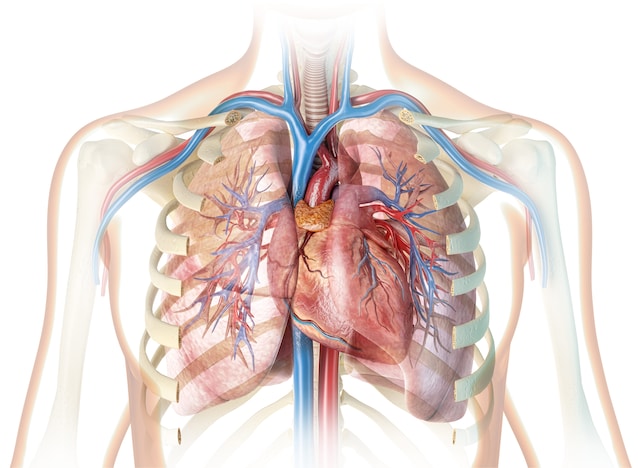

Hjertet kan konseptuelt assimileres til en pumpe. Det er faktisk en muskel som veksler to faser: den av avslapning og sammentrekning. Takket være denne rytmiske mekanismen mottar hjertet blod lavt i oksygen, sender det til lungene for å oksygenere det og pumper den deretter igjen i resten av kroppen, og starter syklusen igjen. Hjertets struktur er delt inn i To distinkte halvdel – Høyre og venstre – bare for å skille de to blodstrømmene, og garanterer effektiv sirkulasjon.

Denne sirkulasjonen er muliggjort av hjertekontraksjoner, som finner sted helt autonomt, uten behov for bevisst kontroll. Hjertet er faktisk en ufrivillig muskel. Men hvordan finner denne spontane sammentrekningen sted? Gjennom Elektriske impulser.

Hjertet er delt inn i to seksjoner, hver sammensatt av en lobbysom ønsker blodet velkommen og fra en ventrikkelsom setter ham tilbake i sirkulasjonen. En ventil er mellom atrium og ventrikkel som garanterer riktig blodstrøm.